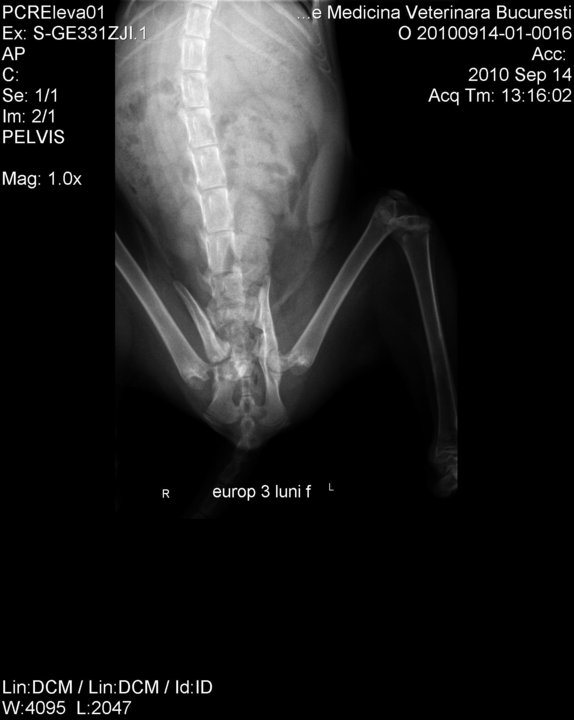

This is how the poor thing looked when they found her. Notice the broken and dislocated hips, pushing inside the abdominal cavity and pressing onto her organs.